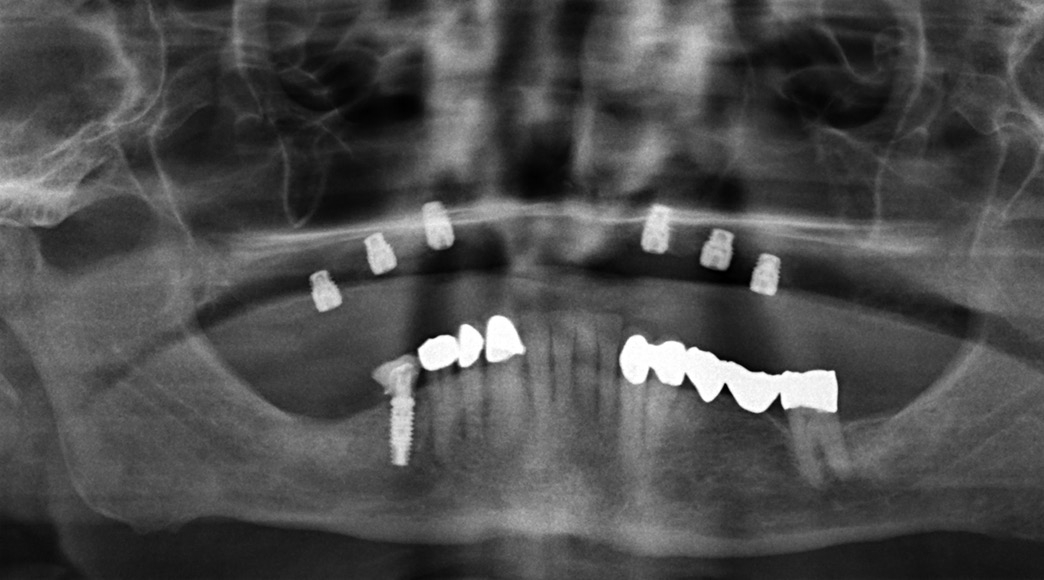

Aufgrund der hochgradigen Atrophie des Kieferknochens war für die geplante implantatprothetische Versorgung eine absolute Kieferkammerhöhung notwendig. Nach gründlicher Anamnese und Patientenaufklärung begann die Behandlung.

Erweitertes Backward Planning